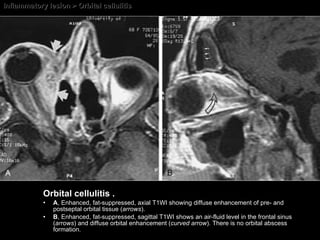

Orbital Cellulitis  Orbital cellulitis = M/C cause of proptosis in children. M/C cause of orbital cellulitis = Sinusitis. M/C organism = Bacteria. M/ C bacteria = Staphylococcus, Streptococcus Pneumococcus, Pseudomonas, Neisseriaceae, Haemophilus, and mycobacteria. M/C virus =  Herpes simplex and herpes zoster.

Inflammatory lesion > Orbital cellulitis Orbital cellulitis . A , Enhanced, fat-suppressed, axial T1WI showing diffuse enhancement of pre- and postseptal orbital tissue ( arrows ).  B , Enhanced, fat-suppressed, sagittal T1WI shows an air-fluid level in the frontal sinus ( arrows ) and diffuse orbital enhancement ( curved arrow ). There is no orbital abscess formation.